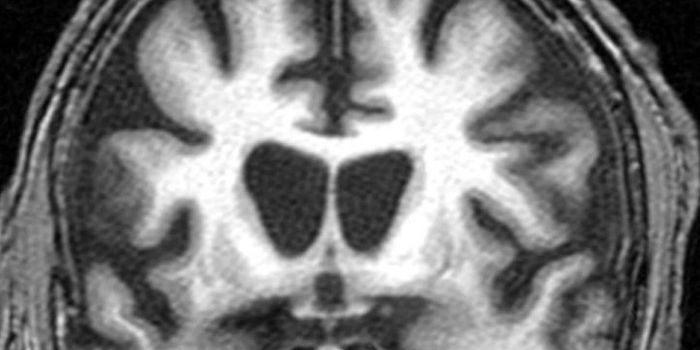

MAY 05, 2020Clinical & Molecular DXImagine a future where we could “see” inside the human brain at stunning high resolution, detecting the earl ...

JUN 28, 2017CancerBrain imaging via MRIs may soon be enhanced with simple sugar instead of conventional metal complexes. A new study found ...

DEC 03, 2020NeuroscienceTo obtain high-resolution images of the brain, researchers usually need to reduce the thickness of the skull or cut into ...